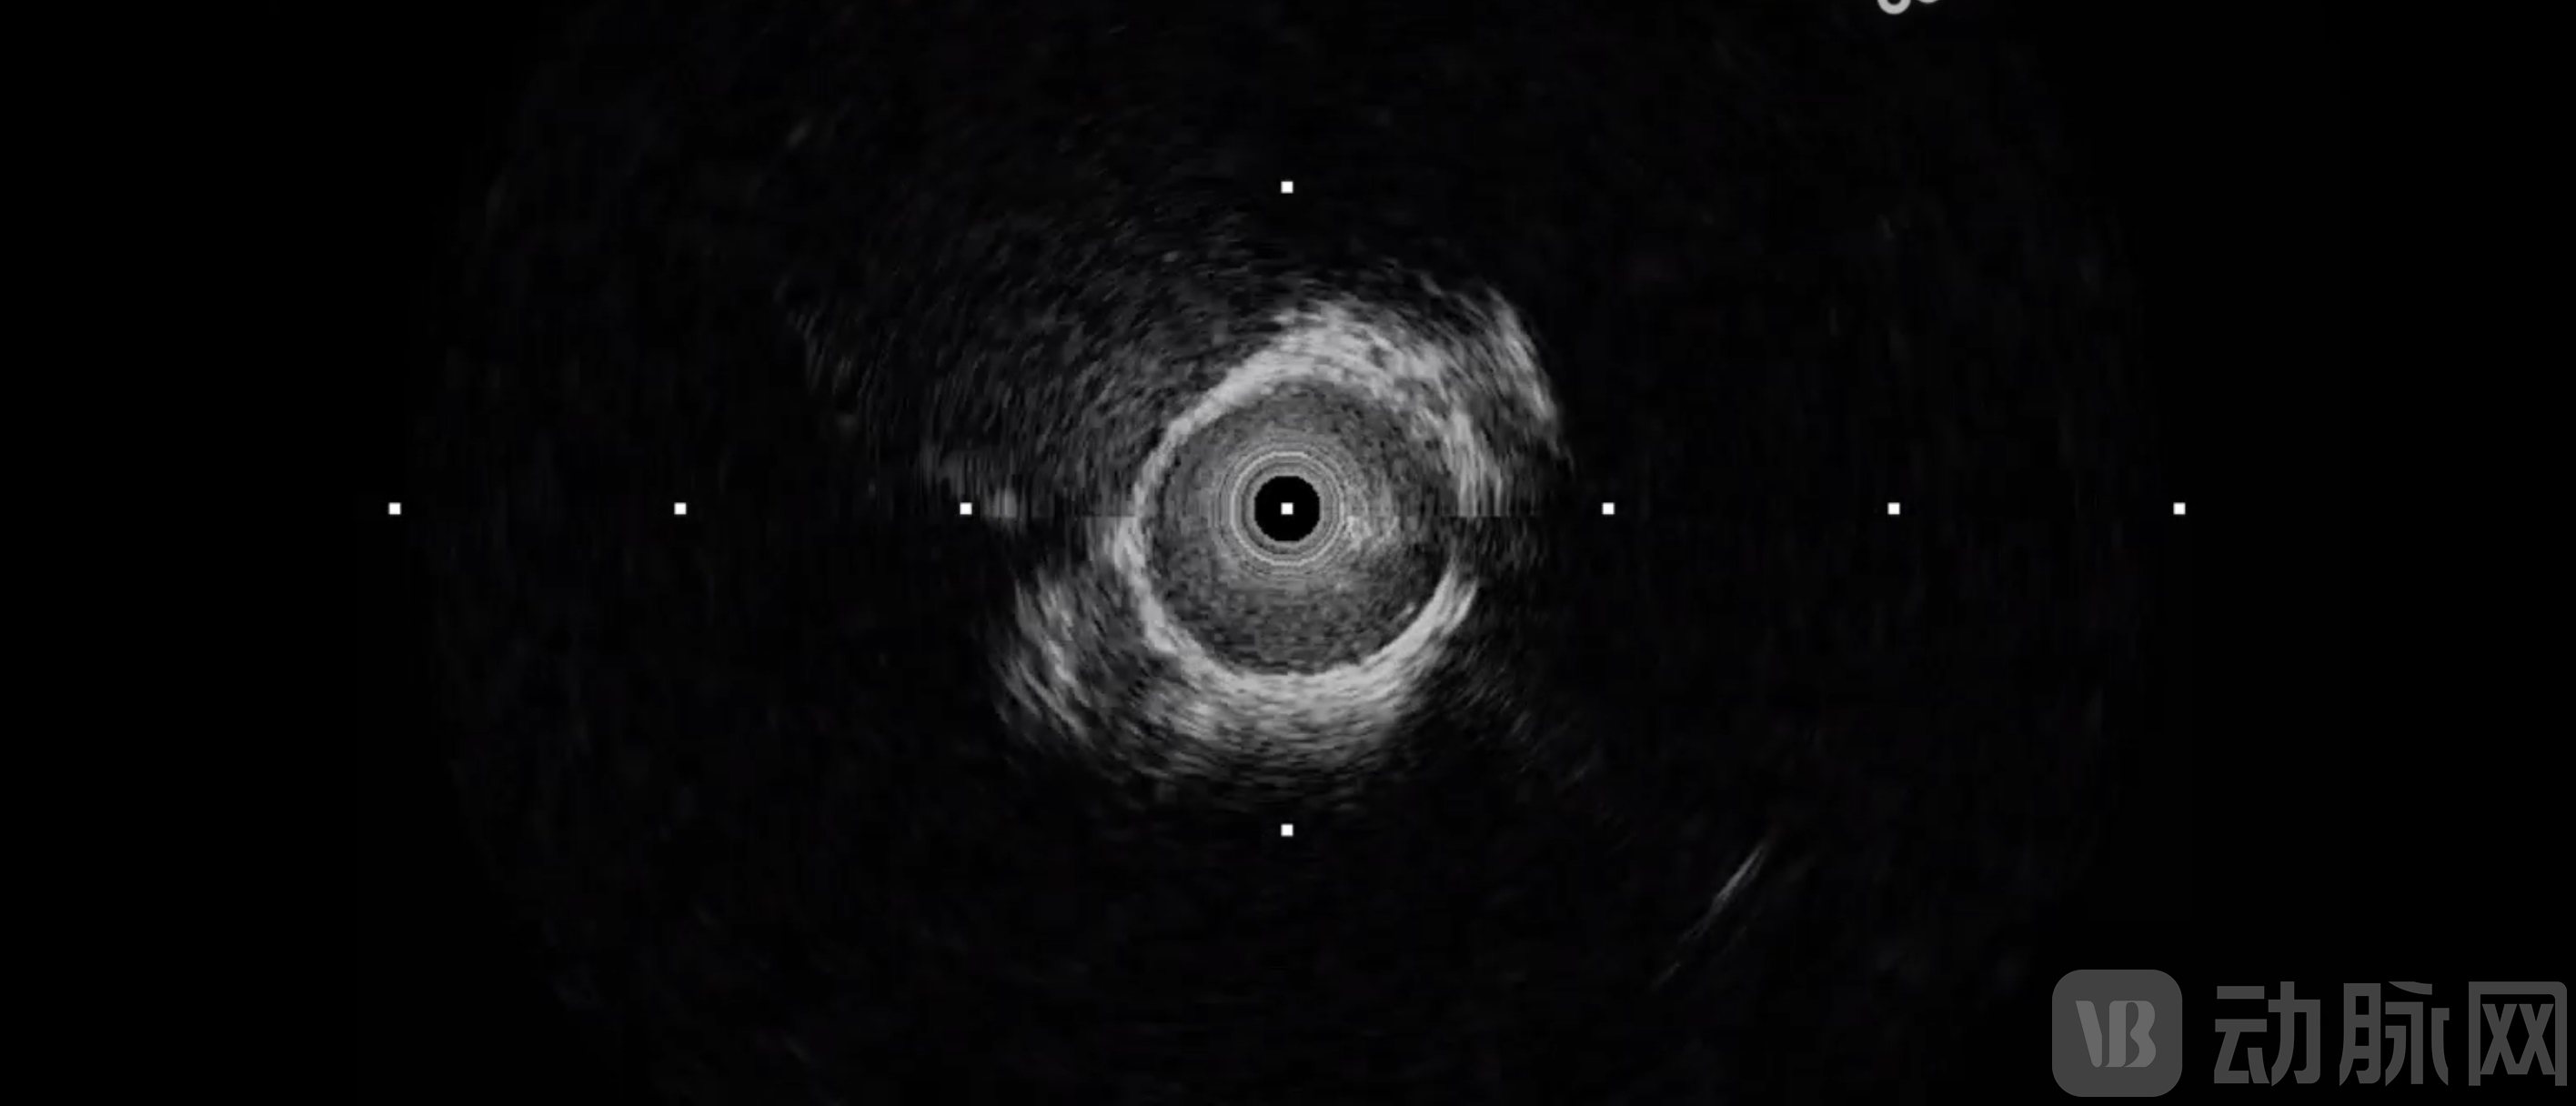

图为Neuro-IVUS脑血管成像图像

作为专为颅内血管优化的腔内影像技术,Neuro-IVUS搭载了0.42mm×0.53mm的超微型超声换能器(约头发丝直径的二分之一),成功突破了传统IVUS导管无法进入2mm脑血管的物理极限;其首创的AI抗干扰算法可有效过滤颅骨伪影,实现在4-8mm穿透深度下的高分辨率成像,攻克了“只见管腔、不见管壁”的影像盲区,填补了全球脑血管内超声诊疗技术的空白。

AI抗干扰算法,克服颅骨屏障。高频探头虽分辨率高,但穿透力随频率升高而衰减。因而鑫云生科研发了AI抗干扰算法,以弥补高频的穿透短板。其通过深度学习模型过滤颅骨伪影,在不牺牲分辨率的前提下,实现了颅骨干扰环境下的高清成像,填补了传统DSA“管腔-only”成像的不足。